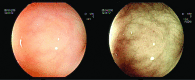

Figure 1.

Gastric ulcer. Endoscopic view after administration of N-acetyl cysteine and methylene blue dye.

Figure 2.

NBI images of gastric ulcer.